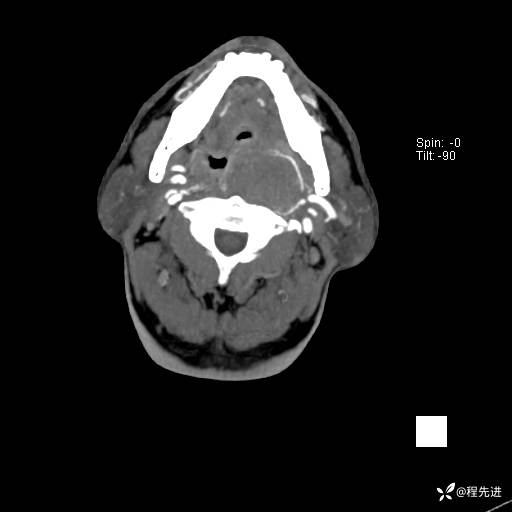

CT平扫:

CT增强:

动脉期:

静脉期: